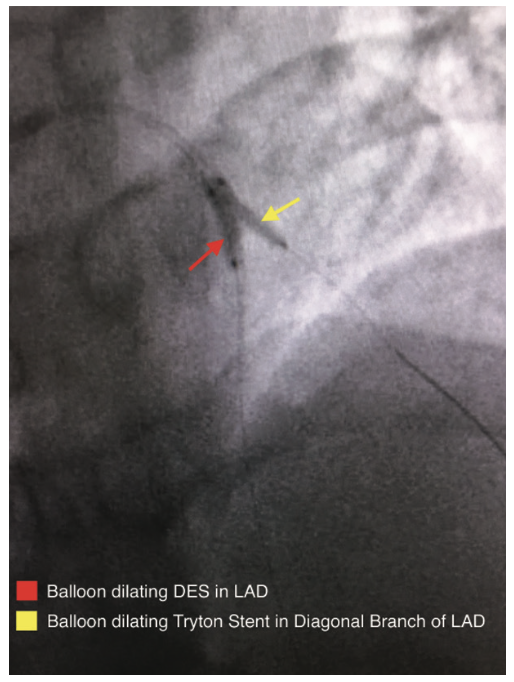

A coronary angiogram was performed, revealing a critical bifurcation stenosis of the mid left anterior descending artery (LAD) and a large diagonal branch vessel which was felt to be the culprit vessel causing her symptoms (Figure 3). Using the CorPath from a 6 French radial approach, a guidewire was placed across the lesion into the diagonal branch of the LAD and a second guidewire was placed across the lesion into the mid LAD (Figure 4). After pre-dilating the lesion, the CorPath was used to measure the longitudinal length of the diagonal branch at the ostium. An appropriately sized Tryton stent was placed over the diagonal branch guidewire and advanced to the site of the lesion. The stent was then carefully advanced by utilizing the CorPath such that the mid-markers precisely straddled the ostium of the diagonal branch to within 1 mm (Figure 5). The Tryton stent delivery system balloon was inflated and the stent was successfully deployed in an appropriate position (Figure 6). The Tryton stent balloon was withdrawn and the diagonal branch guidewire was rewired through the transition zone of the Tryton stent into the main vessel distal to the ostium of the diagonal branch, taking care not to retract proximal to the Tryton stent. Once the guidewire was successfully placed in the LAD through the transition zone, the “trapped” original LAD guidewire was removed (Figure 7). The length needed for the LAD stent was measured from the proximal edge of the Tryton stent to beyond the distal edge of the LAD lesion, and a drug-eluting stent (DES) was advanced over the same guidewire into position within the main branch zone of the Tryton stent and extending into the LAD, and then deployed. After removal of the DES balloon, an additional guidewire was selected and advanced into the diagonal branch, taking care to ensure that it was advanced within the lumen of the LAD stent. Two appropriately sized balloons were selected and advanced into position in the diagonal branch and LAD along their respective guidewires. Simultaneous kissing balloon inflation was performed (Figure 8). Repeat angiography confirmed adequate stent expansion and demonstrated dramatic improvement in coronary perfusion (Figure 9).